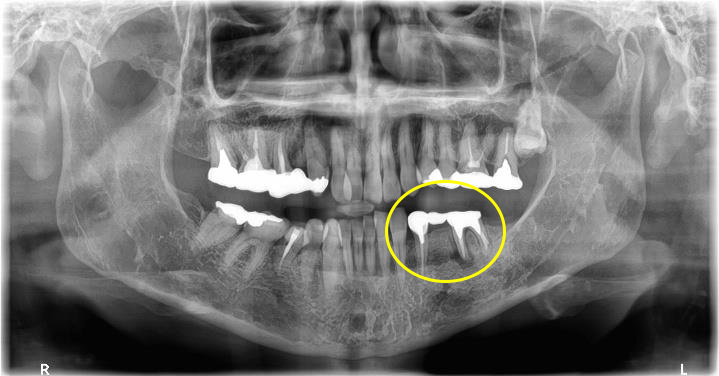

患者さまは「奥歯の歯ぐきが腫れている」「咬むと違和感がある」とのことで来院されました。

検査を行ったところ、奥歯には強い負担がかかっており、歯の根が折れてしまっている状態(歯根破折)でした。

残念ながらこの状態では歯を残すことが難しく、抜歯が必要でした。

この症例では、抜歯する歯の周囲で骨が少し痩せている状態でした。

そのため、インプラントをしっかり支えるために、骨造成(骨を補う治療)を同時に行い、インプラントを埋入しました。

術前の状態

一次手術後のレントゲン写真です。

吸収していた骨の部分は人工の骨を足すことで無事に回復することができています。